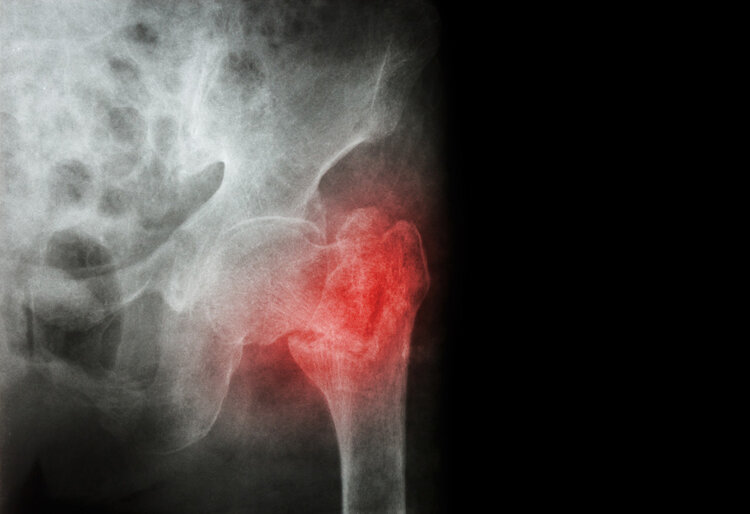

髋部骨折 , 医生都知道 , 这对一个80岁的老人绝对是危及生命的打击 。 好在覃奶奶被第一时间送到医院 , 才保住了一条性命 。

临床上 , 老年人摔倒了从此卧床不起 , 甚至危及生命的例子数不胜数 。 为什么老年人摔倒了这么容易骨折?上年纪后 , 骨密度下降 , 骨质疏松、肌肉萎缩越来越严重 , 使髋关节处于十分脆弱的状态 , 一旦受到外力的冲击 , 发生摔倒、滑倒 , 或者身体大幅度扭转 , 股骨近端就会受到损伤 , 导致股骨颈骨折 。

“人生最后一次骨折”

浙大二院骨科创伤病区副主任李伟栩提醒 , 骨折本身不致命 , 但骨折引起的各种并发症如肺部感染、褥疮、尿路感染、血栓栓塞等却会要人命 。 据统计 , 老年髋部骨折一年死亡率可达50% 。 因此 , 髋部骨折也被称为老人的“人生最后一次骨折” 。

伤筋动骨一百天 , 骨折发生之后 , 老年人翻身和坐起会变得十分困难 , 大部分需要长期卧床 , 容易导致呼吸系统感染、泌尿系统感染、血栓和褥疮等并发症 , 严重的还会造成休克、瘫痪 , 甚至危及生命 , 十分危险 。